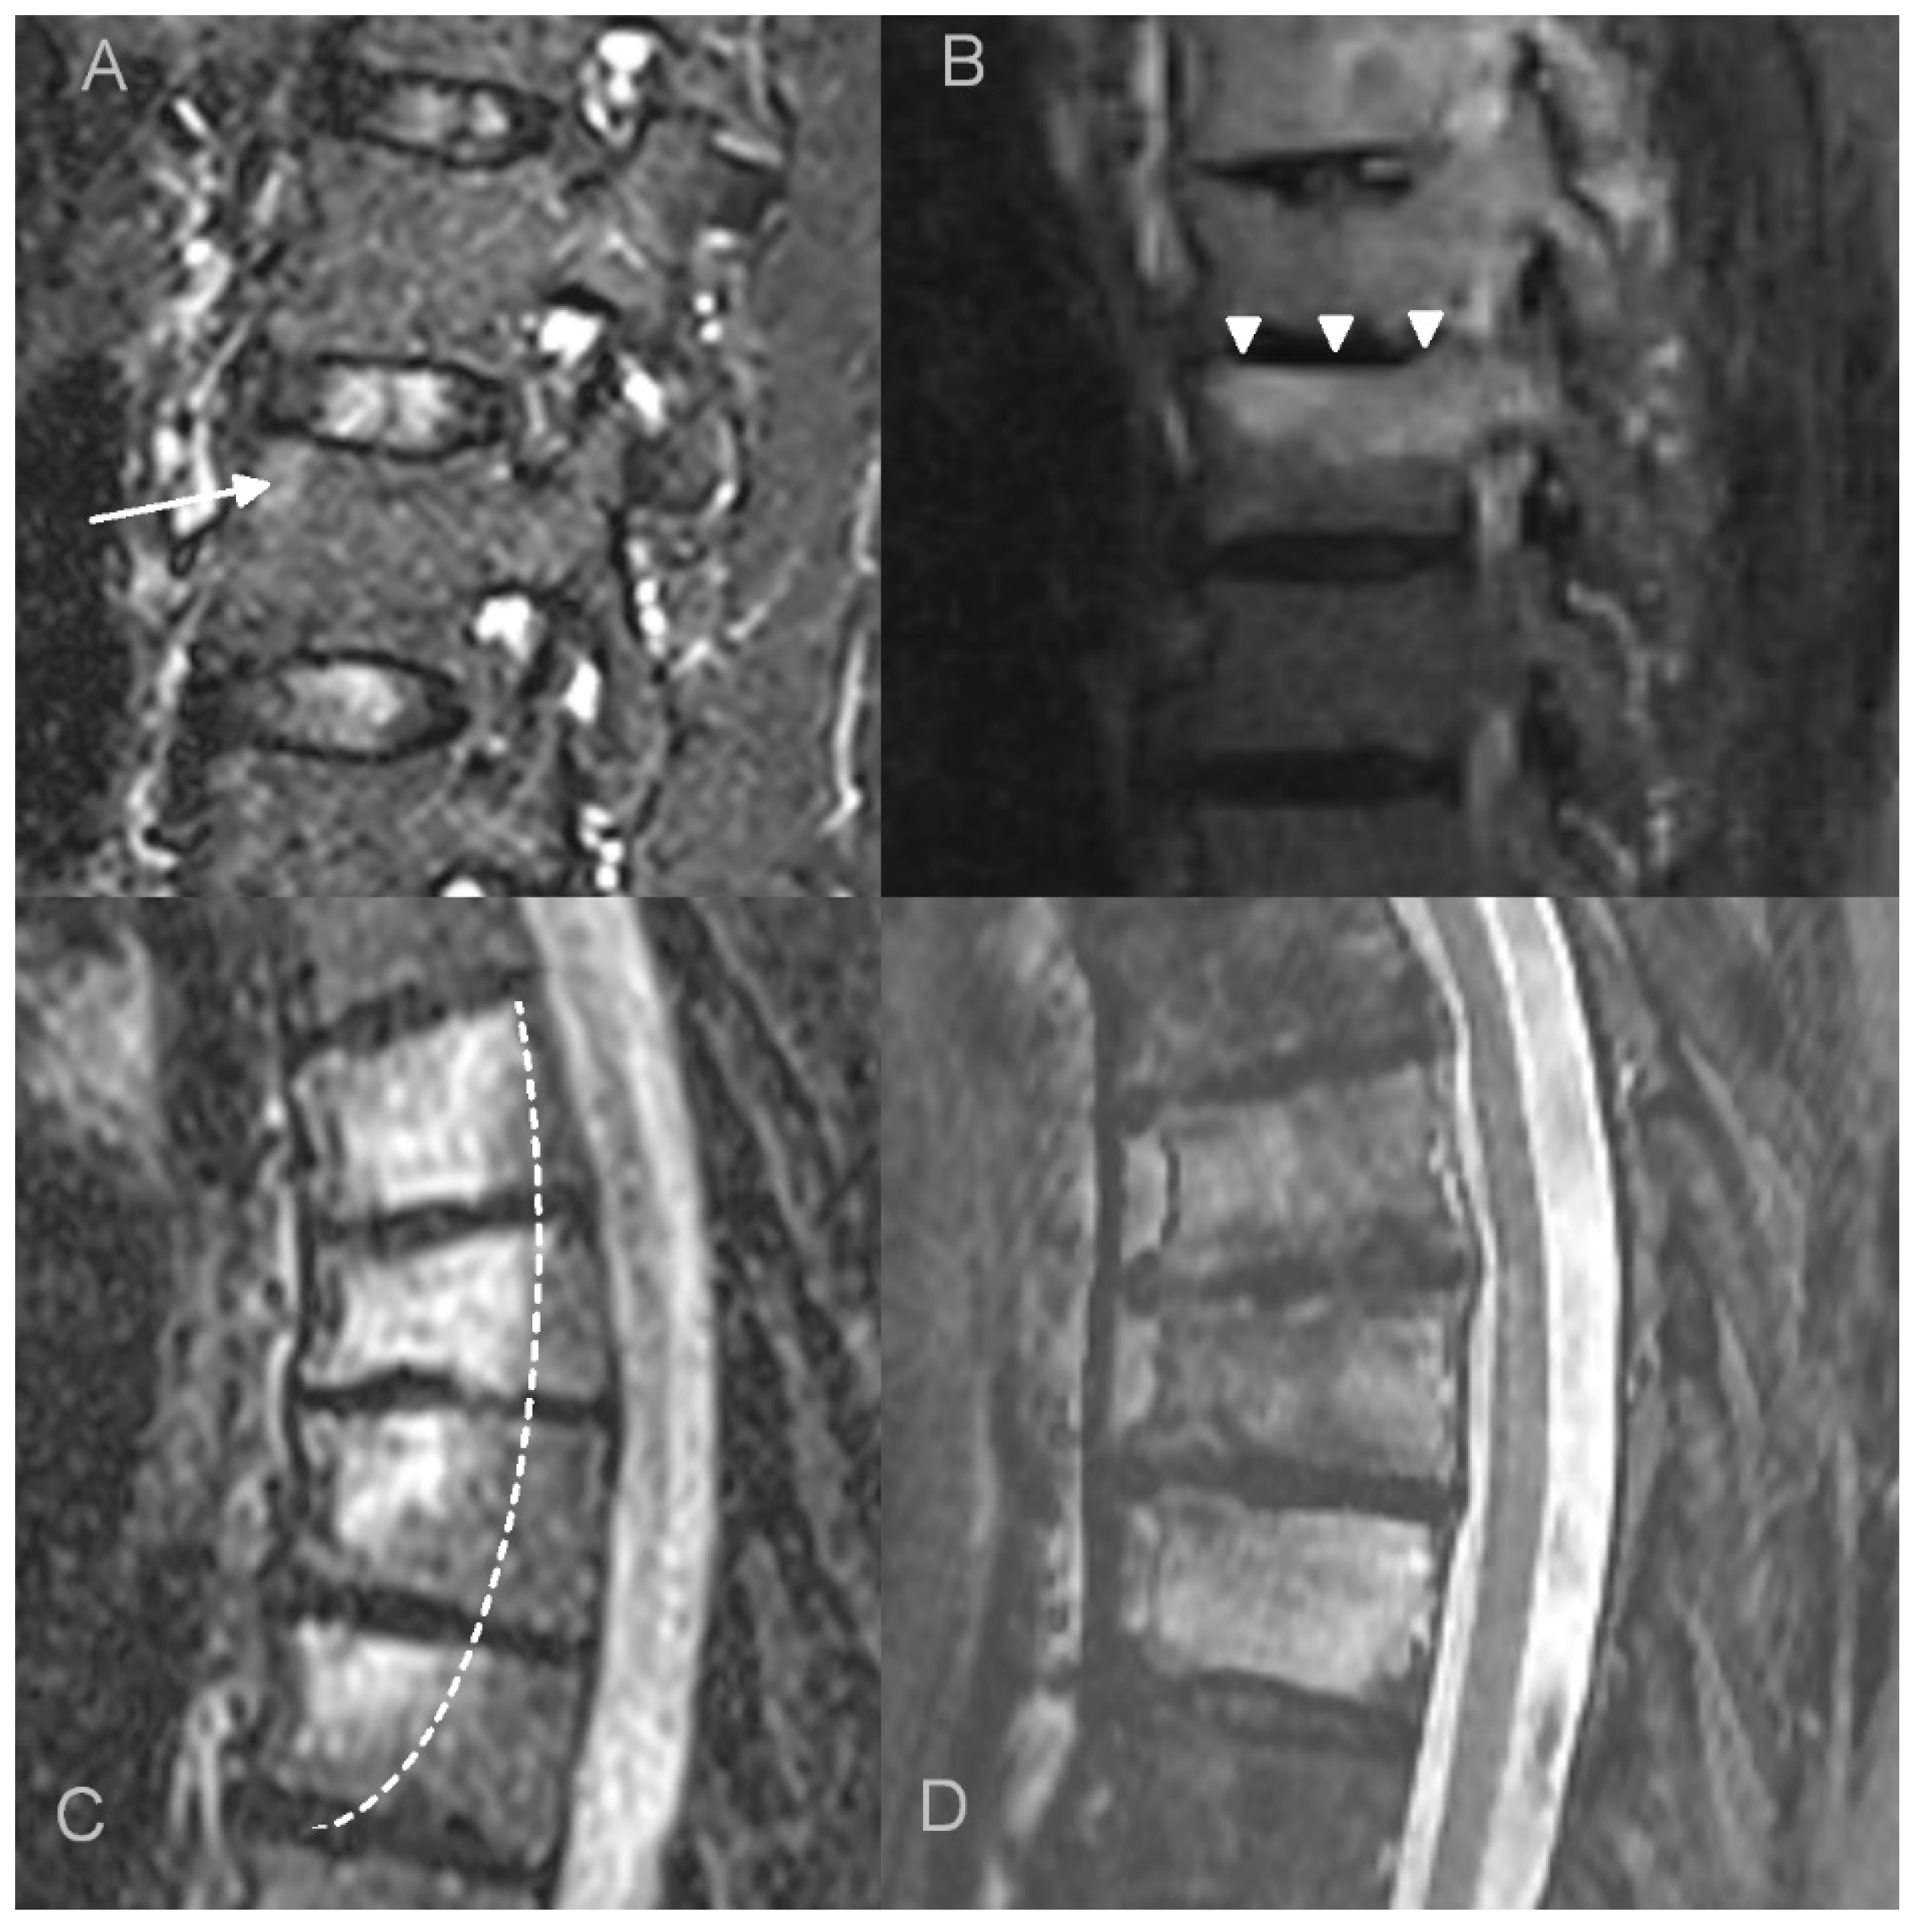

- bone marrow edema (BME) presence and pattern (Figure 1):

Figure 1. Bone marrow edema (BME) patterns appreciated on T2 FS/STIR MRI images. (A). corner inflammatory lesions (arrow); (B). propagating (arrowheads); (C). semicircular/curvilinear (dotted line); (D). diffuse—patchy (in the upper two vertebrae) and solid (in the lowest vertebra).- vertebral body corner inflammatory lesions (CIL)—active Romanus lesion defined as small foci of BME at the vertebral corners,